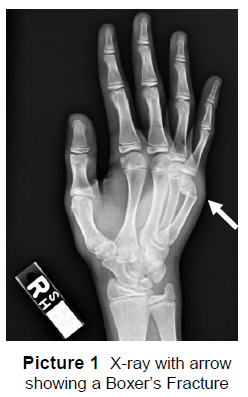

Denne fraktur er en stabil skade. Vi forventer ikke, at den forværres. Den behandles sikkert med hånden i en velcrobøjle (billede 2). Skinnebøjlen sættes på hånden for at hjælpe med at holde knoglen beskyttet og holde håndleddet og fingrene i ro, mens knoglen heler.

Dit barn skal bære velcroskinnebøjlen i 3 uger fra det tidspunkt, hvor det bliver set i klinikken.

• Bøjlen skal kun tages af for at tage brusebad, bad eller anden hygiejne og derefter mindst en gang dagligt for at kontrollere huden for irritation eller rødme.

• Hold altid bøjlen ren og tør.

• Dit barn kan deltage i sport, gymnastik og andre fysiske aktiviteter, mens det bærer velcrobøjlen. 3 uger efter kan dit barn vænne sig ud af bøjlen, når der ikke længere er smerter, hvis der trykkes på området over mellemgulvet. Der er ikke behov for nogen formel opfølgning.